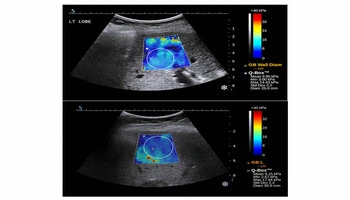

Endoscopic Ultrasonography (EUS)

Endoscopic Ultrasonography (EUS) is an advanced imaging modality that combines endoscopy with high-frequency ultrasound to provide detailed visualization of the gastrointestinal wall layers and adjacent organs. It plays a critical role in evaluating pancreatic diseases, biliary disorders, submucosal tumors, lymph nodes, and mediastinal lesions that are difficult to assess with conventional imaging.

EUS offers superior resolution compared to CT and MRI for detecting small pancreatic tumors, cystic lesions, neuroendocrine tumors, and early malignancies. It is also invaluable for staging gastrointestinal cancers and assessing the depth of tumor invasion, guiding appropriate treatment strategies.

Endoscopic Ultrasonography

FNA & FNB

Fine Needle Aspiration (FNA) and Fine Needle Biopsy (FNB)

Fine Needle Aspiration (FNA) and Fine Needle Biopsy (FNB) allow accurate tissue diagnosis of pancreatic masses, lymph nodes, and deep-seated tumors with minimal risk.

LAMS

Lumen-Apposing Metal Stents (LAMS)

Lumen-Apposing Metal Stents (LAMS) enable minimally invasive drainage of pancreatic pseudocysts and walled-off necrosis, avoiding open surgery.

Biliary Drainage

EUS-Guided Hepaticogastrostomy

EUS-Guided Hepaticogastrostomy, EUS guided choledochoduodenostomy and EUS guided cholecystogastrostomy provides internal biliary drainage when ERCP fails.

Pain Relief

EUS-Guided Celiac Plexus Neurolysis

EUS-Guided Celiac Plexus Neurolysis offers effective pain relief in chronic pancreatitis and pancreatic cancer.